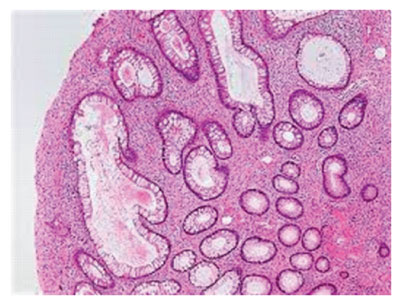

Upon microscopic examination, juvenile polyp characteristically exhibits an abundant, oedematous lamina propria incorporated with inflammatory cells. Superficial mucosa is layered with cuboidal to columnar epithelium along with cystic dilatation of glandular epithelium demonstrating reactive alterations such as non–neoplastic or hamartomatous modifications and epithelial retention [1,2]. Distended glandular articulations appear pervaded with mucus along with inspissation of debris and inflammatory cells [1,2].

Figure 1: Juvenile polyp demonstrating cystic dilatation of glandular articulations, superimposed layer of columnar epithelium and circumscribing stroma infiltrated by chronic inflammatory cells [5].

Figure 2: Juvenile polyp depicting cystic dilatation of glandular articulations layered with mucus-secreting columnar epithelium and an encompassing stroma infiltrated with chronic inflammatory cells and focal red cell extravasation [6].